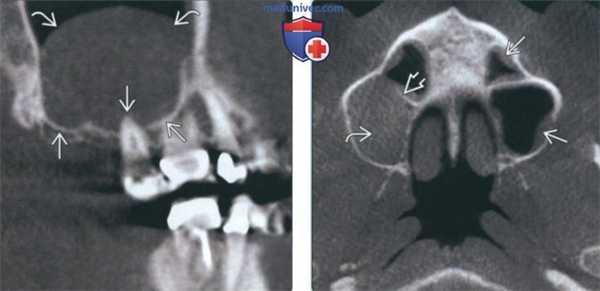

Рис. 1. КЛКТ. Панорамная (а) и мультипланарные реконструкции правого (б) и левого (в) верхнечелюстных синусов пациента М., 37 лет. Диагноз: двусторонний одонтогенный хронический верхнечелюсной синусит. Отмечаются КТ-признаки хронического гранулематозного периодонтита зубов 1.8, 2.7, 2.8 (в виде очагов деструкции у верхушек корней, округлой формы, с четкими ровными контурами). Нижние костные стенки синусов истончены, не прослеживаются в области периодонта зубов 1.8 и 2.8 (указаны стрелками). В нижнем отделе правого верхнечелюстного синуса определяется пристеночное мягкотканное образование гомогенной структуры с полицикличным верхним контуром. Левый верхнечелюстной синус субтотально заполнен мягкотканным содержимым гомогенной структуры с округлым верхним контуром.